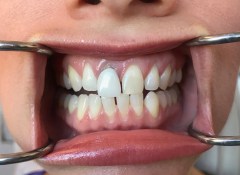

#8 e.max crown